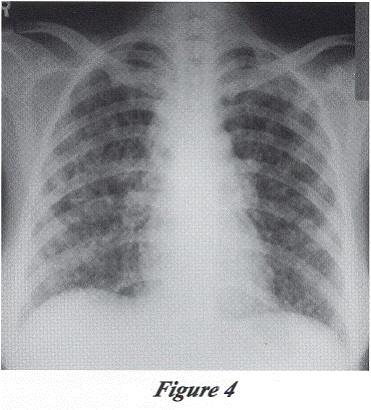

Our patient had human immunodeficiency virus infection complicated by active tuberculosis involving the lungs and cervical lymph node. She showed initially satisfactory clinical and radiological response to anti-tuberculous treatment. After about seven weeks’ of anti-tuberculous treatment and three weeks’ of antiretroviral therapy, her clinical and radiological state deteriorated. Extensive septic work up did not show any other focus of infection. While continuing anti-tuberculous drugs, antiretroviral therapy, and commencing broad-spectrum antibiotics, high dose Septrin and high dose steroid, she gradually improved.